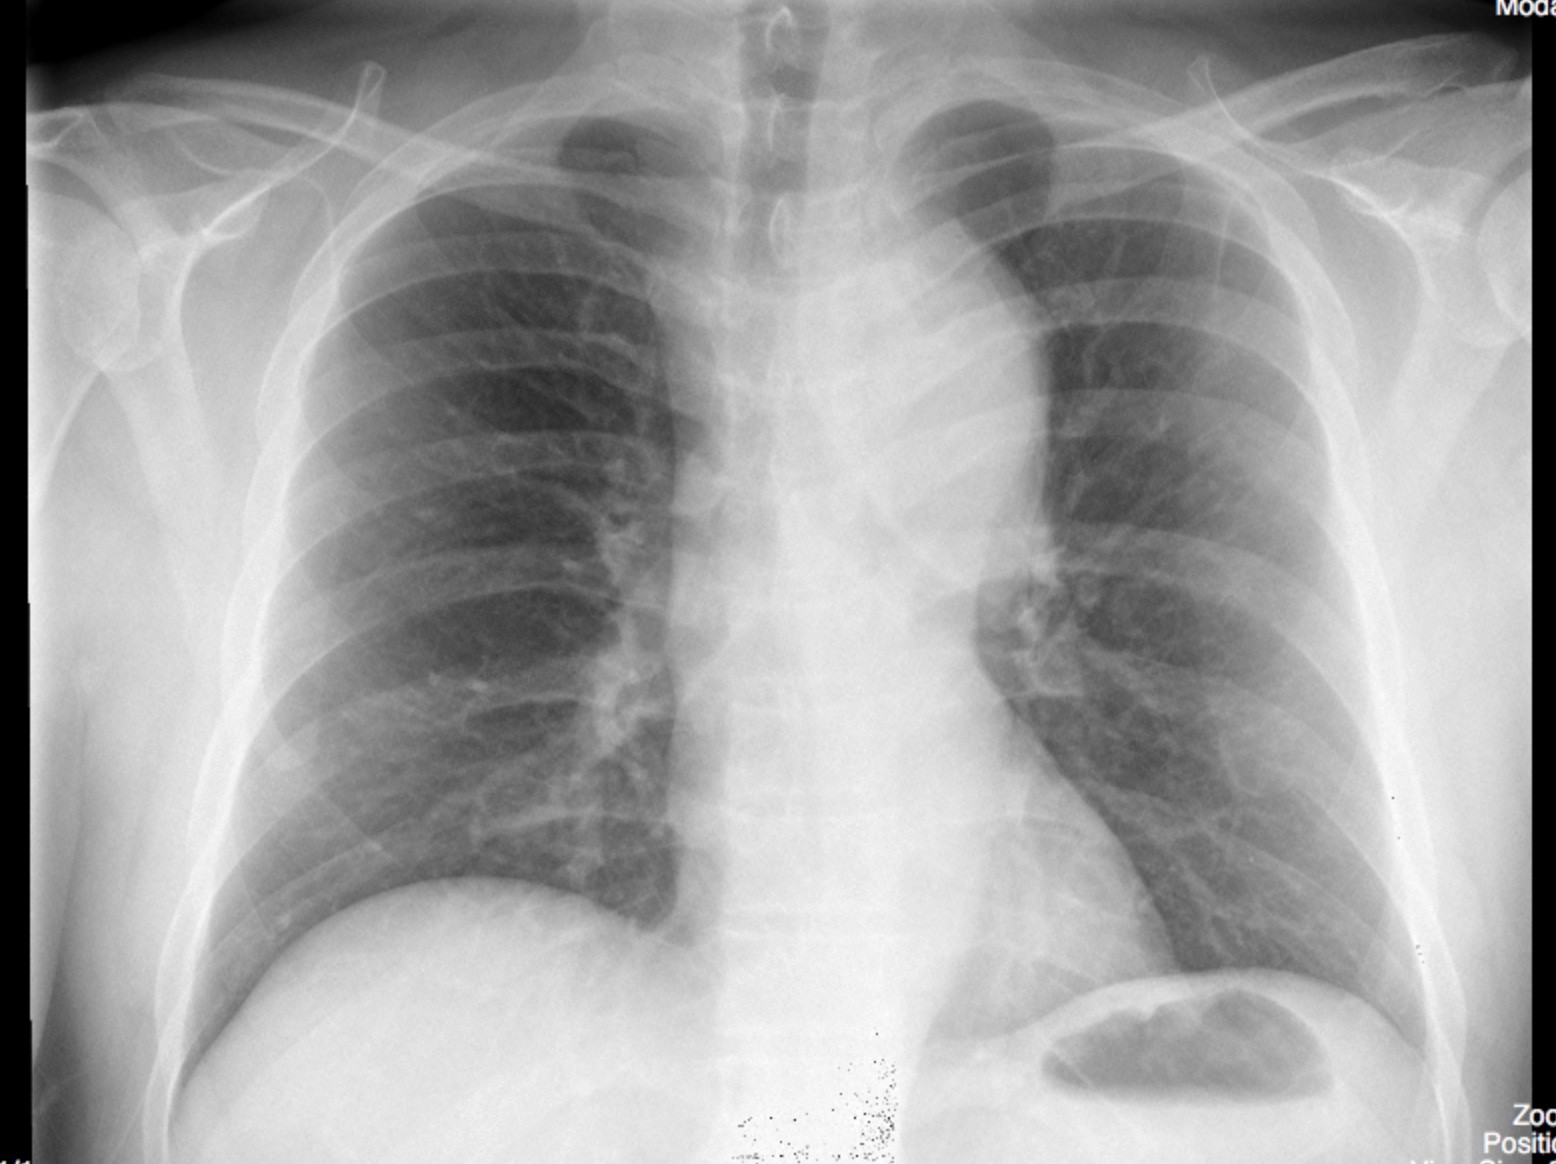

A 49-year old man arrives to the emergency department looking unwell. He had sudden onset of abdominal pain two hours earlier that moved up to his chest. He is anxious, distressed and feels like he could die.

This 49-year old male had abdominal and chest pain that start while smoking cocaine. This is on top of a history of untreated hypertension. On exam, he has signs of aortic dissection and requires stabilization before going to the CT scanner. Upon arrival back from the CT scan (which confirms the diagnosis of Type A aortic dissection) the patient is altered and in shock. Assessment reveals the patient to be in cardiac tamponade requiring emergent pericardiocentesis.